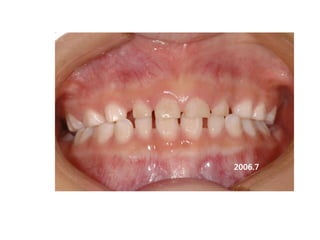

1999.04.05/F

C.C

• Diastema, flattened lower ant.

Dx

• Mentalis action, heavy labial frenum

Goal

• Establish normal lip tone

2006.02.08

2004.05.13

2006.12.27 10m

2007.05.08 1y 3m

2008.07.30 2y 5m

2009. 02.18.3y

2009.08.11 3y6m

2010.06.15 4y4m

2012 02 01

out of Tr 2yr